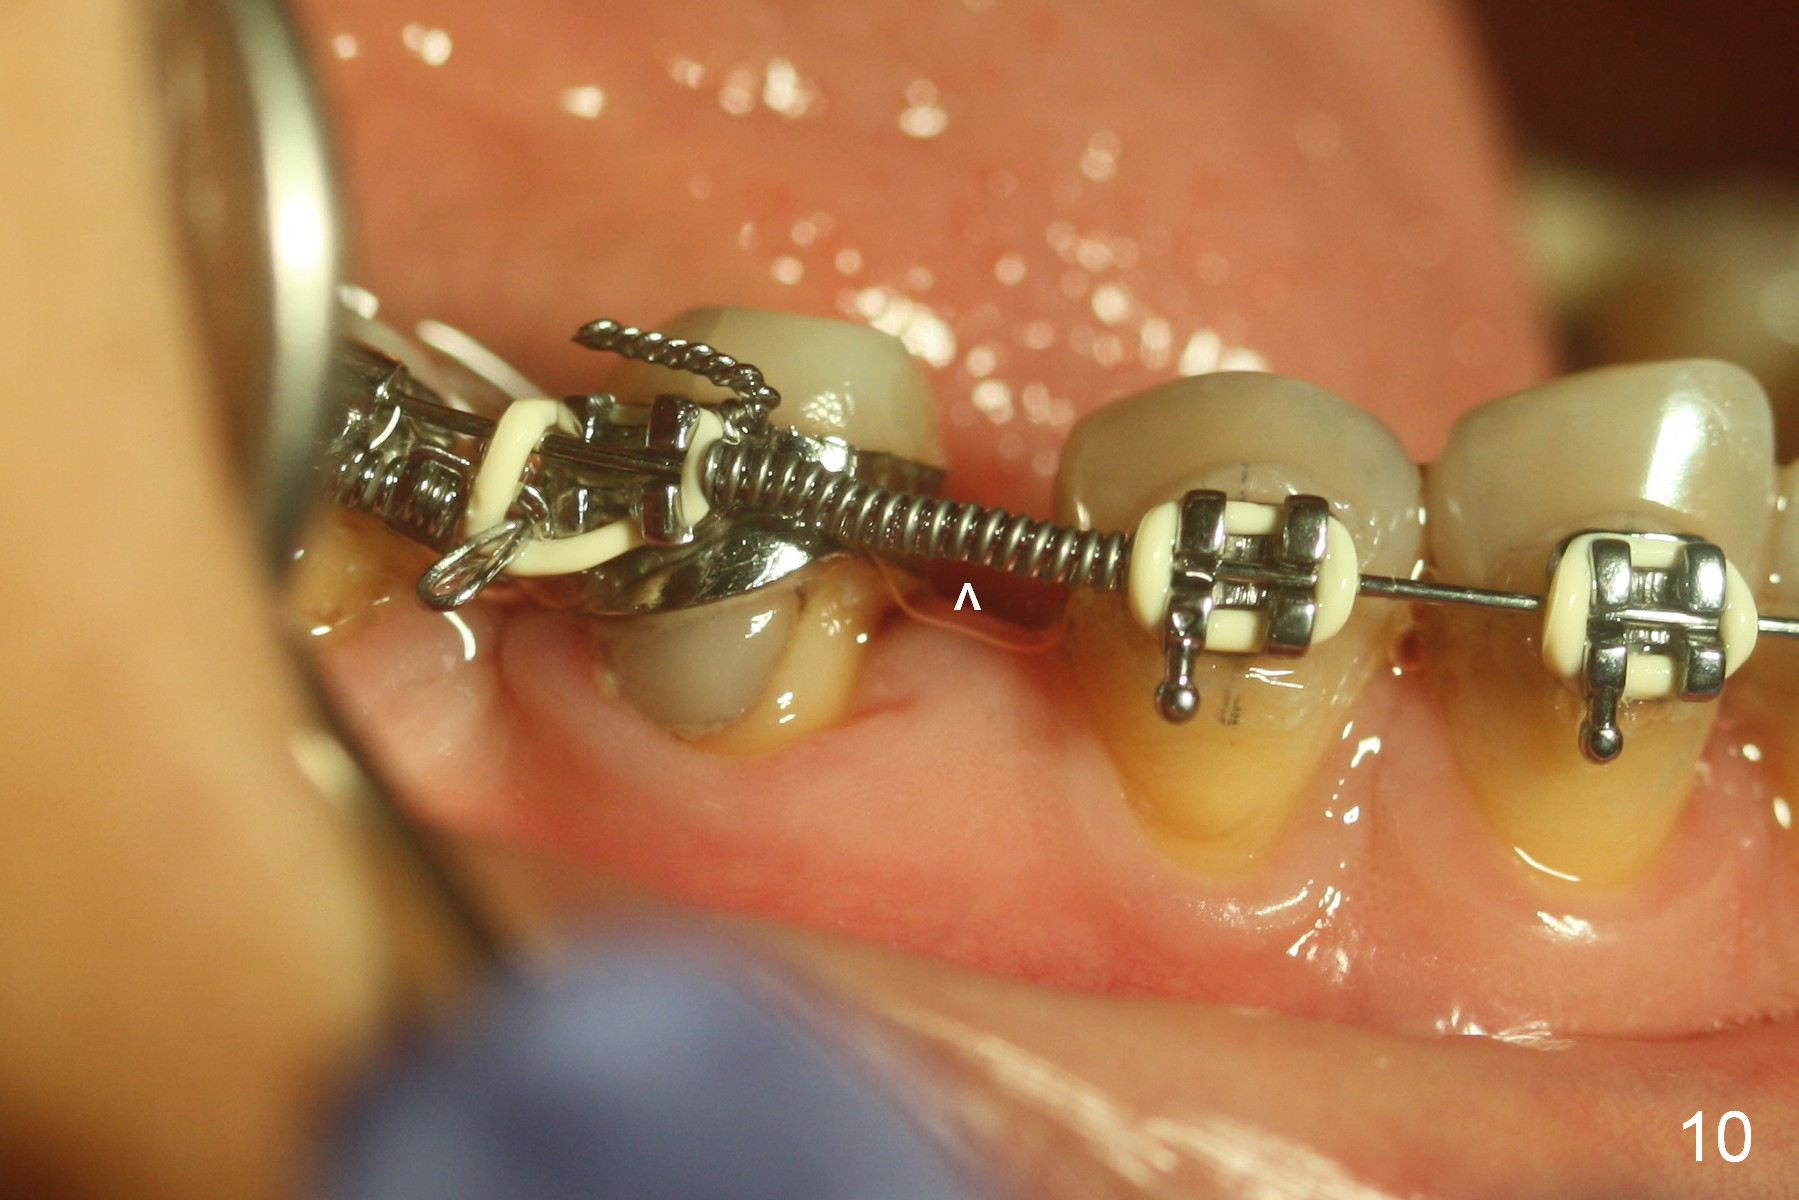

A 47-year-old lady has lost the lower right 1st molar for long time; with reduction of the buccolingual width (Fig.1) and mesiodistal width (Fig.2,3). With regional orthodontic appliance (Fig.4) for 3 months, the tooth #29 has started being distalized (Fig.5). One month and a half later, the tooth #26 starts to shift labially. Power chains and then closed coil spring are placed between #29 and 32. #29 distalization is slow (Fig.7) with closure of the diastema between #31 and 32 (Fig.8, as compared to Fig.1,3). Seven months post banding, a 10 mm miniimplant is placed distobuccal to the tooth #32 (Fig.6); the same 12-mm closed spring is stretched distal by ~ 6 mm (Fig.8 between arrowheads). Two months later, #29 is more distalized (Fig.9 tilted) with bone deposit mesially (*) and coronally (^). A .018' stainless steel wire is installed with an open coil spring placed between #28 and 29 (Fig.10 (^),11). Note #29 rotation (Fig.11). To solve the tilting, a power hook (Fig.12 black) will be clamped to a .016x.016 wire (red), while the closed spring is lowered and attached to the power hook (Fig.12 white). Take photos after removing the existing wire occlusally to show the alveolar width change. When the wire is placed, make sure that the distal wings of #29 bracket is fully engaged to reduce the tooth rotation. Make occlusal adjustment on #31 and 32 to reduce anterior open bite.